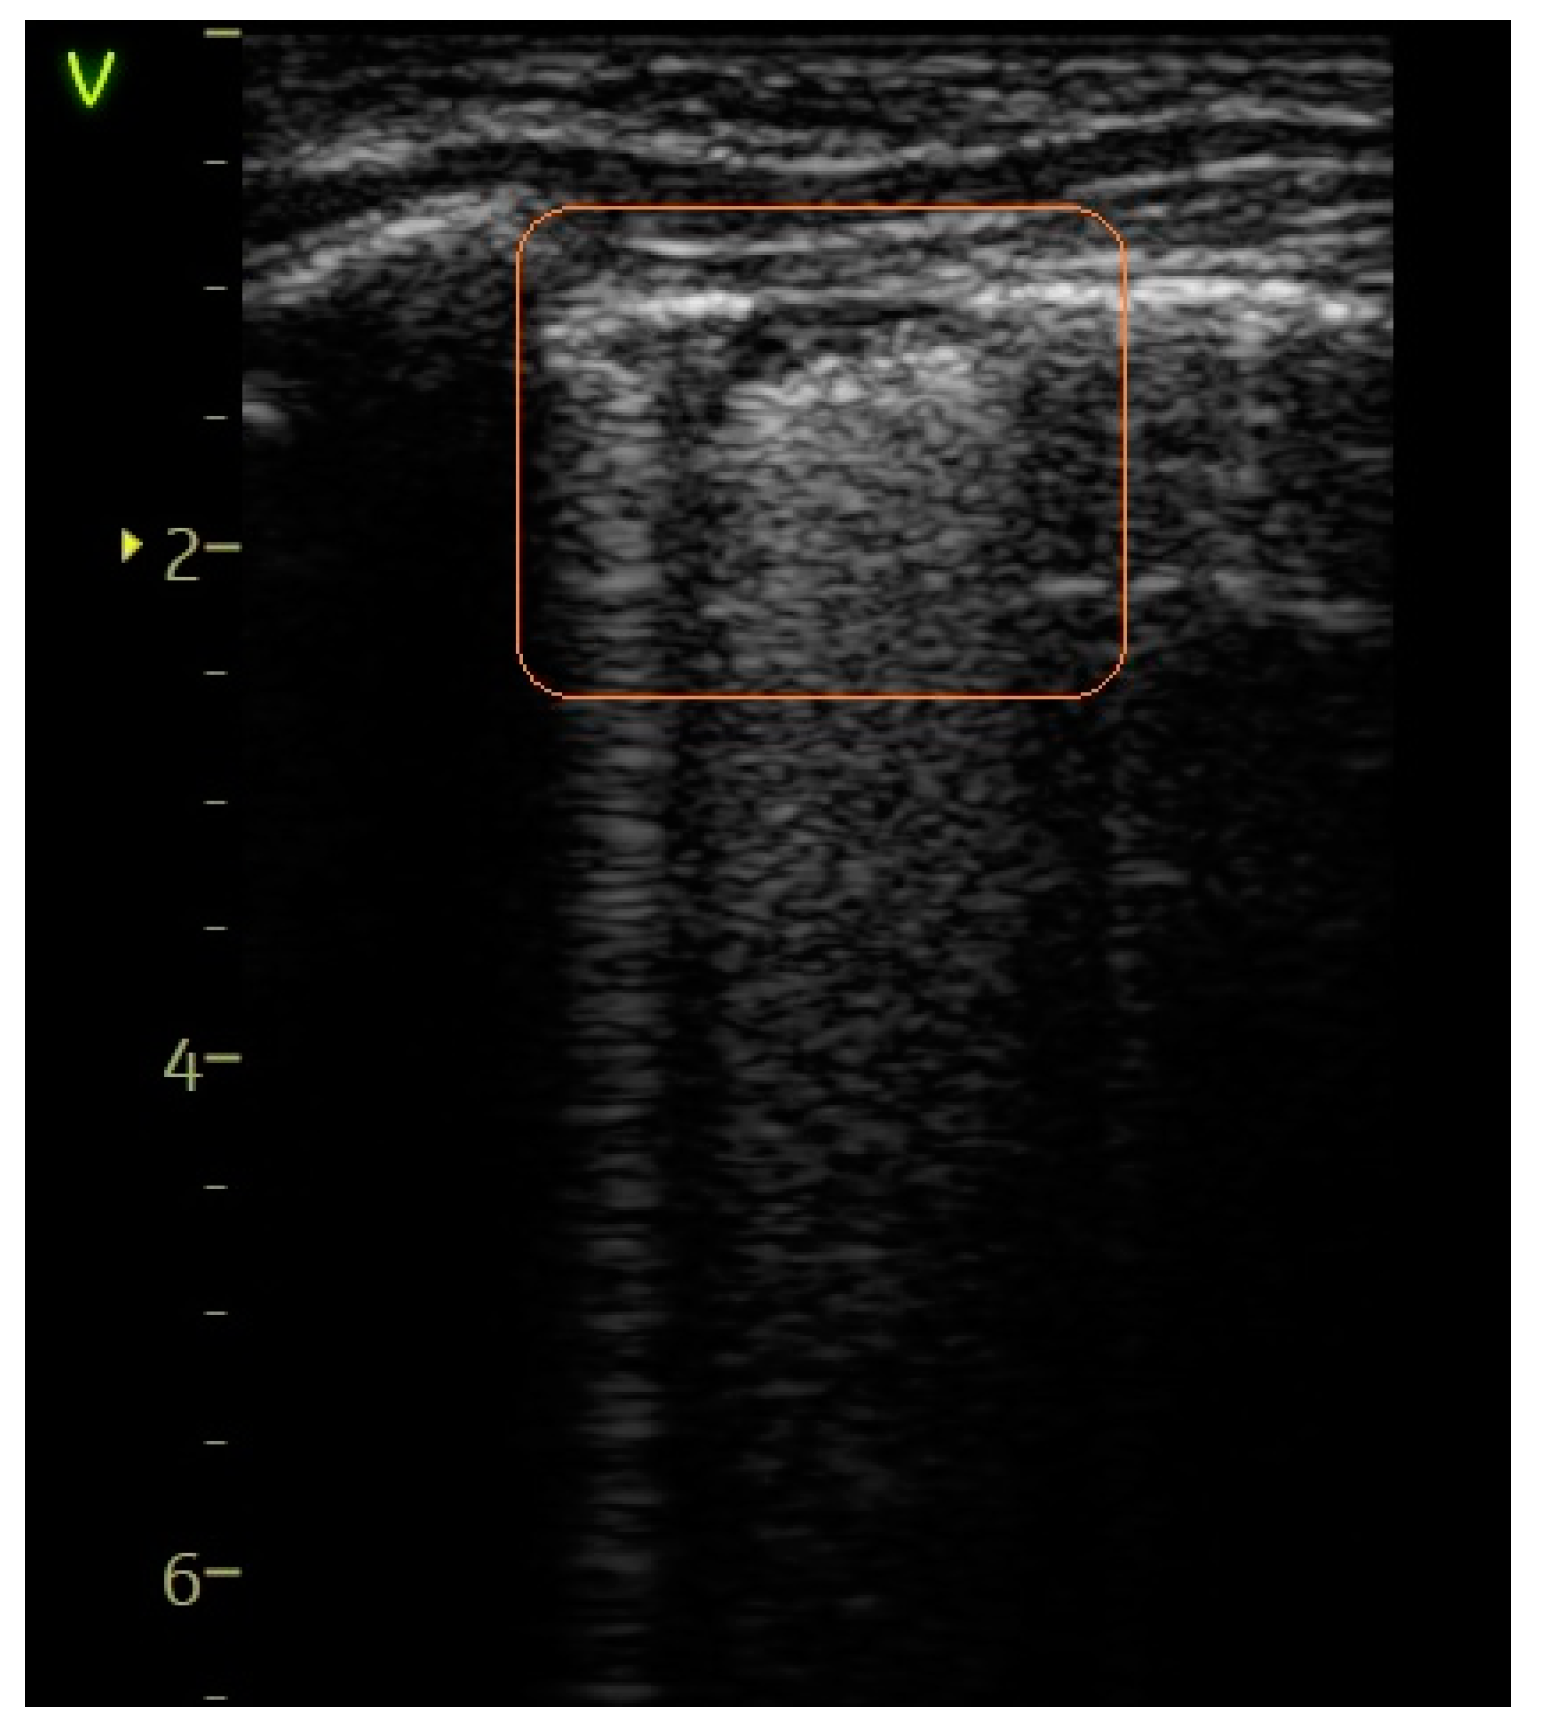

- A score of 1 indicated the observation of more than two B-lines (referred to as sparse B-lines) per intercostal space, accompanied by pleural abnormalities, such as irregularities or thickening.

| Confluent B-lines—Figure 4, Figure 5 and Figure 6 | 23 (31.08%) | 10 (90.91%) | 59.83% | 14.26 | 0.0002 |

| Pleural abnormalities—Figure 4 and Figure 5 | 24 (32.43%) | 9 (81.82%) | 49.39% | 9.72 | 0.001 |